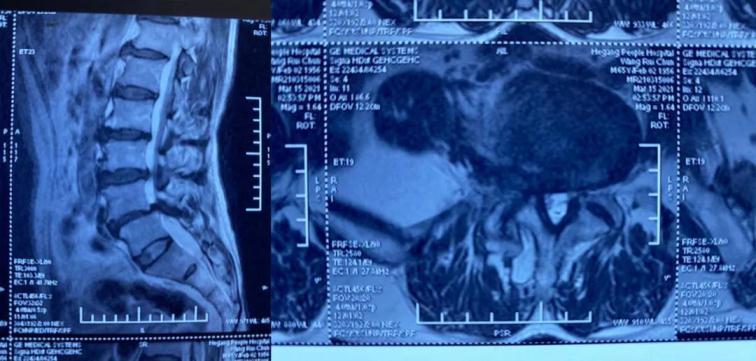

患者王某,男,65歲,腰痛伴右下肢麻痛1年,坐起及行走時(shí)疼痛明顯加重,行走不足100米即疼痛難忍需要休息,保守治療無(wú)效,嚴(yán)重影響生活質(zhì)量。慕名來(lái)到我院并找到喬院長(zhǎng)尋求治療?;颊呷朐汉?,經(jīng)過喬院長(zhǎng)認(rèn)真細(xì)致的檢查,診斷為:腰椎管狹窄、腰椎滑脫。

術(shù)前MRI